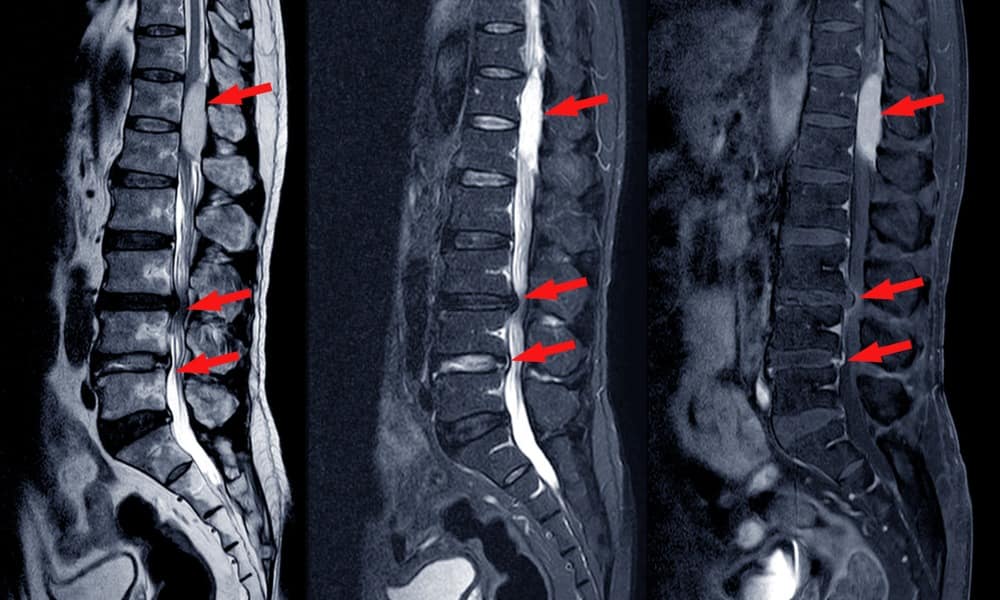

From www.alamy.com